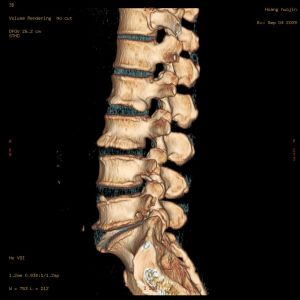

腰椎病檢測圖本病最基本的病因是腰椎間盤的退行性改變。正常椎間盤富有彈性和韌性,具有強大抗壓能力,可承擔450千克的壓力而無損傷。但在20歲以後椎間盤即開始逐漸退變,髓核含水量逐漸減少,椎間盤的彈性和抗負荷能力也隨之減退,在這種情況下,因各種負荷的作用,椎間盤易在受力最大處,即纖維環的後部,由里向外產生裂隙,在此基礎上,某些因素可誘發纖維環的破裂,導致髓核組織突出或脫出。腰椎的骨性結構(椎體、椎弓根、椎板、橫突、棘突)圍成的椎管、椎間孔構成神經通道,韌帶、椎間盤、小關節將上述骨性結構聯結在一起,與周圍的肌群共同維持腰椎的穩定和運動

CT檢查:可清晰顯示椎體前、後緣的骨贅,硬脊膜囊、脊髓、神經根的受壓部位和程度,測得椎管前後徑和橫徑,還能了 解椎間孔和橫突孔有無狹小,椎板有無肥厚。